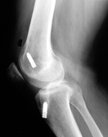

Take a look at the femur (top bone). The white bits are the fixation devices holding the graft in the tunnel. The right X-ray shows the original tunnel (yellow arrow) with the new tunnel behind it and in the correct position. You get an idea of how far anterior the original tunnel was made. If you cannot orientate, look for the patella bone - that is the anterior aspect.